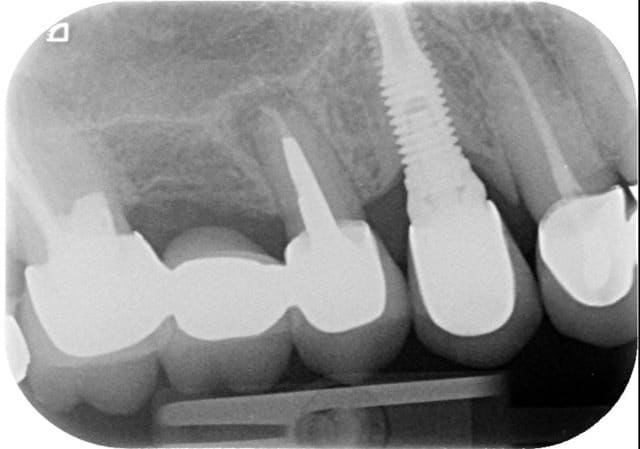

PS: remarquez la petite taille de la racine de 15 et son apex erodé. Une chir apicale d'apres vous? ou une resorption radiculaire d'origine inflammatoire?

> PS: remarquez la petite taille de la racine de 15 et son apex erodé. Une chir

> apicale d'apres vous? ou une resorption radiculaire d'origine inflammatoire?

C'est ce que j'allais te demander, pourquoi cette racine est elle si courte, ni a t'il pas déjà eu une résection apicale?